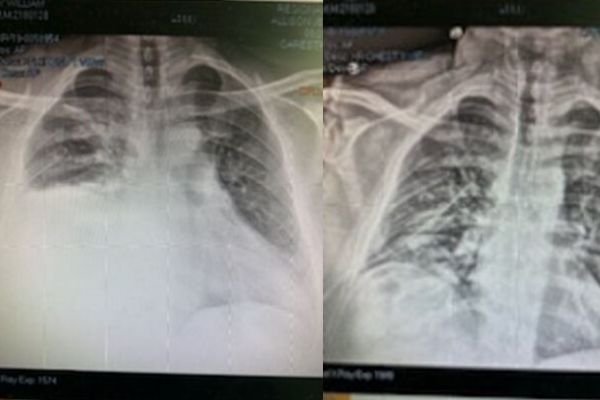

X-rays showing broken ribs Ambulance Scott Finney on Broad Ave before the ride

X-rays Begin

Everyone in trauma was amazing. They begin by checking my neck and spine. Then determining my pelvis and right leg and knee have no breaks. My parents have arrived at this point. My wife's parents arrive just after them. I can feel my ribs shuffling around every time I'm dragged off the bed onto an x-ray or CT scan.

• 6 Broken Ribs on my right side

• Broken Collar Bone on my right side

Later we would learn I had

• Hemothorax – build up of blood between lung and wall of chest

• Pneumothorax – a collapsed right lung